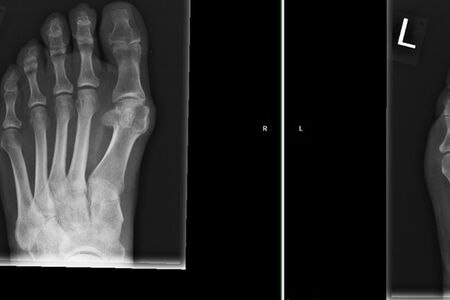

Therapie: distale Umstellung am MT1, Osteotomie an MT 2-4

Die operative Korrektur, bei der Umstellungsosteotomien an den Mittelfußknochen 1-4 links durchgeführt wurden, erfolgte im Mai 2018.

Eine CT Untersuchung ergab eine zeitgerechte Knochenheilung.

Bei anhaltenden Beschwerden wurde im Mai 2019 eine Röntgenaufnahme durchgeführt, die einen Schraubenüberstand von 1mm am Köpfchen des MT3 ergab. Dieser Befund wurde durch eine CT Untersuchung, bei der zusätzlich eine Arthrose im Grundgelenk der Großzehe und der zweiten Zehe gefunden wurde,  bestätigt.